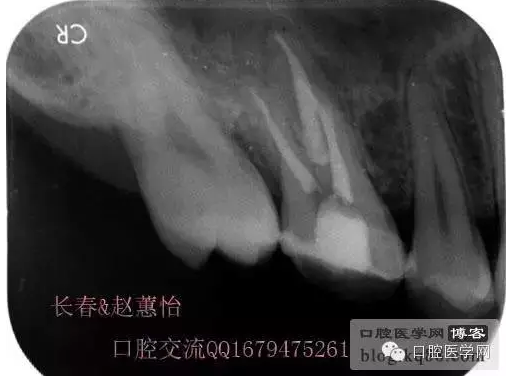

看多了文字眼花繚亂了吧,今天一個根管內(nèi)有臺階的患牙被充填上了,刻意投照了N多的X光片終于有一個給力的了,仔細(xì)觀察,可以看得見喔,也算是辛苦努力給個安慰獎,很多都是從片子上看不出有什么不同的。

這個是術(shù)前照片,一切如常

患牙是死髓牙,患者是一位大學(xué)生,探查根管時一切都很順利,就有點(diǎn)忽視了,當(dāng)然這個臺階是人為造成的,造成的原因呢就是使用機(jī)擴(kuò)時跳號了,所以大家一定要逐號使用啊,預(yù)備出一個臺階,后續(xù)要搭上很長時間才能搞定,好不容易越過臺階下去的銼,一提拉出來就下不去了,著實(shí)讓人郁悶,一切都要從頭再來,這個時候再下銼的時候就必須預(yù)彎了。而且要多角度試探,很是考驗(yàn)?zāi)托牡臅r候。吃一塹長一智嘛!

術(shù)后,明顯可見近中頰側(cè)根管臺階位置

越過臺階后小心預(yù)備直至大錐度銼可以順利進(jìn)術(shù)前片的小彎沒當(dāng)回事,哎